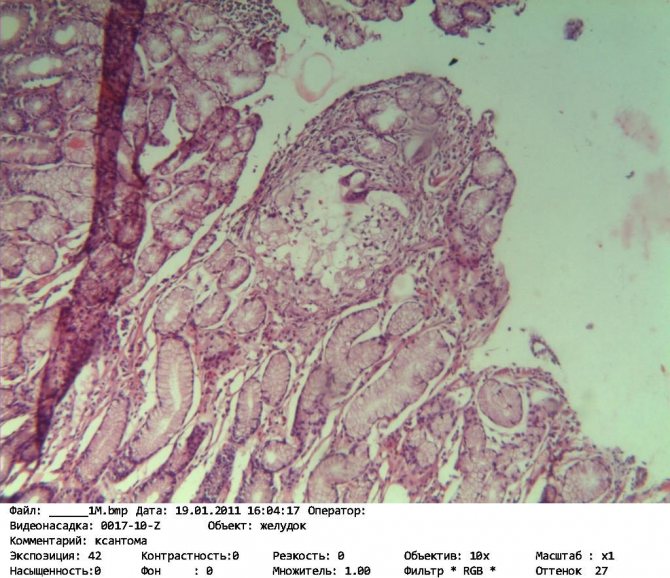

Лечение любого заболевания невозможно представить без изучения его патогенеза. Ксантома является новообразованием доброкачественного характера, которое возникает вследствие нарушения холестеринового обмена. По гистологическому строению это скопление макрофагов. В процессе патологических изменений они захватывают частицы липоидов и трансформируются в ксантомные элементы, образующие опухоли. На слизистой желудка новообразования выглядят как отложения желтоватого цвета с четкими границами. Их размер может варьироваться от 5 до 15 мм.

Ксантома желудка представляет собой небольшое округлое образование, которое незначительно возвышается над поверхностью органа. По своему гистологическому строению она напоминает атеросклеротическую бляшку. Микроскопически образование состоит из множества элементов, в их цитоплазме отчетливо просматриваются жировые включения. Они заполняют практически все пространство клетки, оттесняя ядро и органеллы на периферию. Доброкачественное образование может быть в единственном числе, но чаще встречаются группы бляшек, разбросанных по всем отделам желудка. В этом случае речь идет о заболевании под названием ксантоматоз. Среди наиболее распространенных областей локализации, где можно обнаружить патологию, врачи выделяют следующие:

В слизистой оболочке желудка жиры поглощаются макрофагами. Именно их скопления и образуют ксантому. К отложению жиров более предрасположены поврежденные участки желудка с воспалением и атрофией.